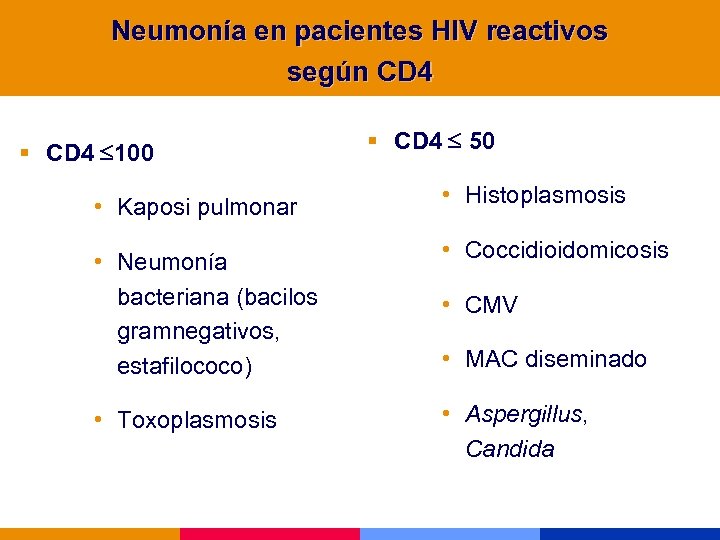

Neumonía en pacientes HIV reactivos según CD 4 § CD 4 500 • Neumonía bacteriana • Neumonía por micobacterias típicas § CD 4 200 • PCP • Cryptococo • Neumonía bacteriana (asociada a bacteriemia/sepsis) • TBC diseminada

Neumonía en pacientes HIV reactivos según CD 4 § CD 4 500 • Neumonía bacteriana • Neumonía por micobacterias típicas § CD 4 200 • PCP • Cryptococo • Neumonía bacteriana (asociada a bacteriemia/sepsis) • TBC diseminada

Neumonía en pacientes HIV reactivos según CD 4 § CD 4 100 § CD 4 50 • Kaposi pulmonar • Histoplasmosis • Neumonía bacteriana (bacilos gramnegativos, estafilococo) • Coccidioidomicosis • Toxoplasmosis • Aspergillus, Candida • CMV • MAC diseminado

Neumonía en pacientes HIV reactivos según CD 4 § CD 4 100 § CD 4 50 • Kaposi pulmonar • Histoplasmosis • Neumonía bacteriana (bacilos gramnegativos, estafilococo) • Coccidioidomicosis • Toxoplasmosis • Aspergillus, Candida • CMV • MAC diseminado